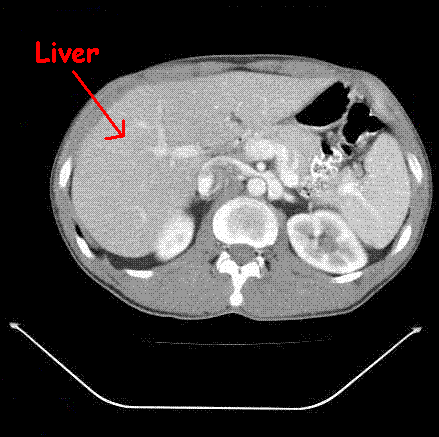

What structure is this?

This structure is the liver.

In relationship to the kidney, the liver falls where anatomically?

The liver is anterior and superior of the kidneys.

When moving from superior to inferior, where does the left kidney begin to manifest as compared to the right kidney? More superiorly, inferiorly, or at the same level?

Under normal conditions, the left kidney will present more superiorly than the right kidney. This is because the liver is on the right side and prevents the right kidney from forming at the same level the left kidney forms at.